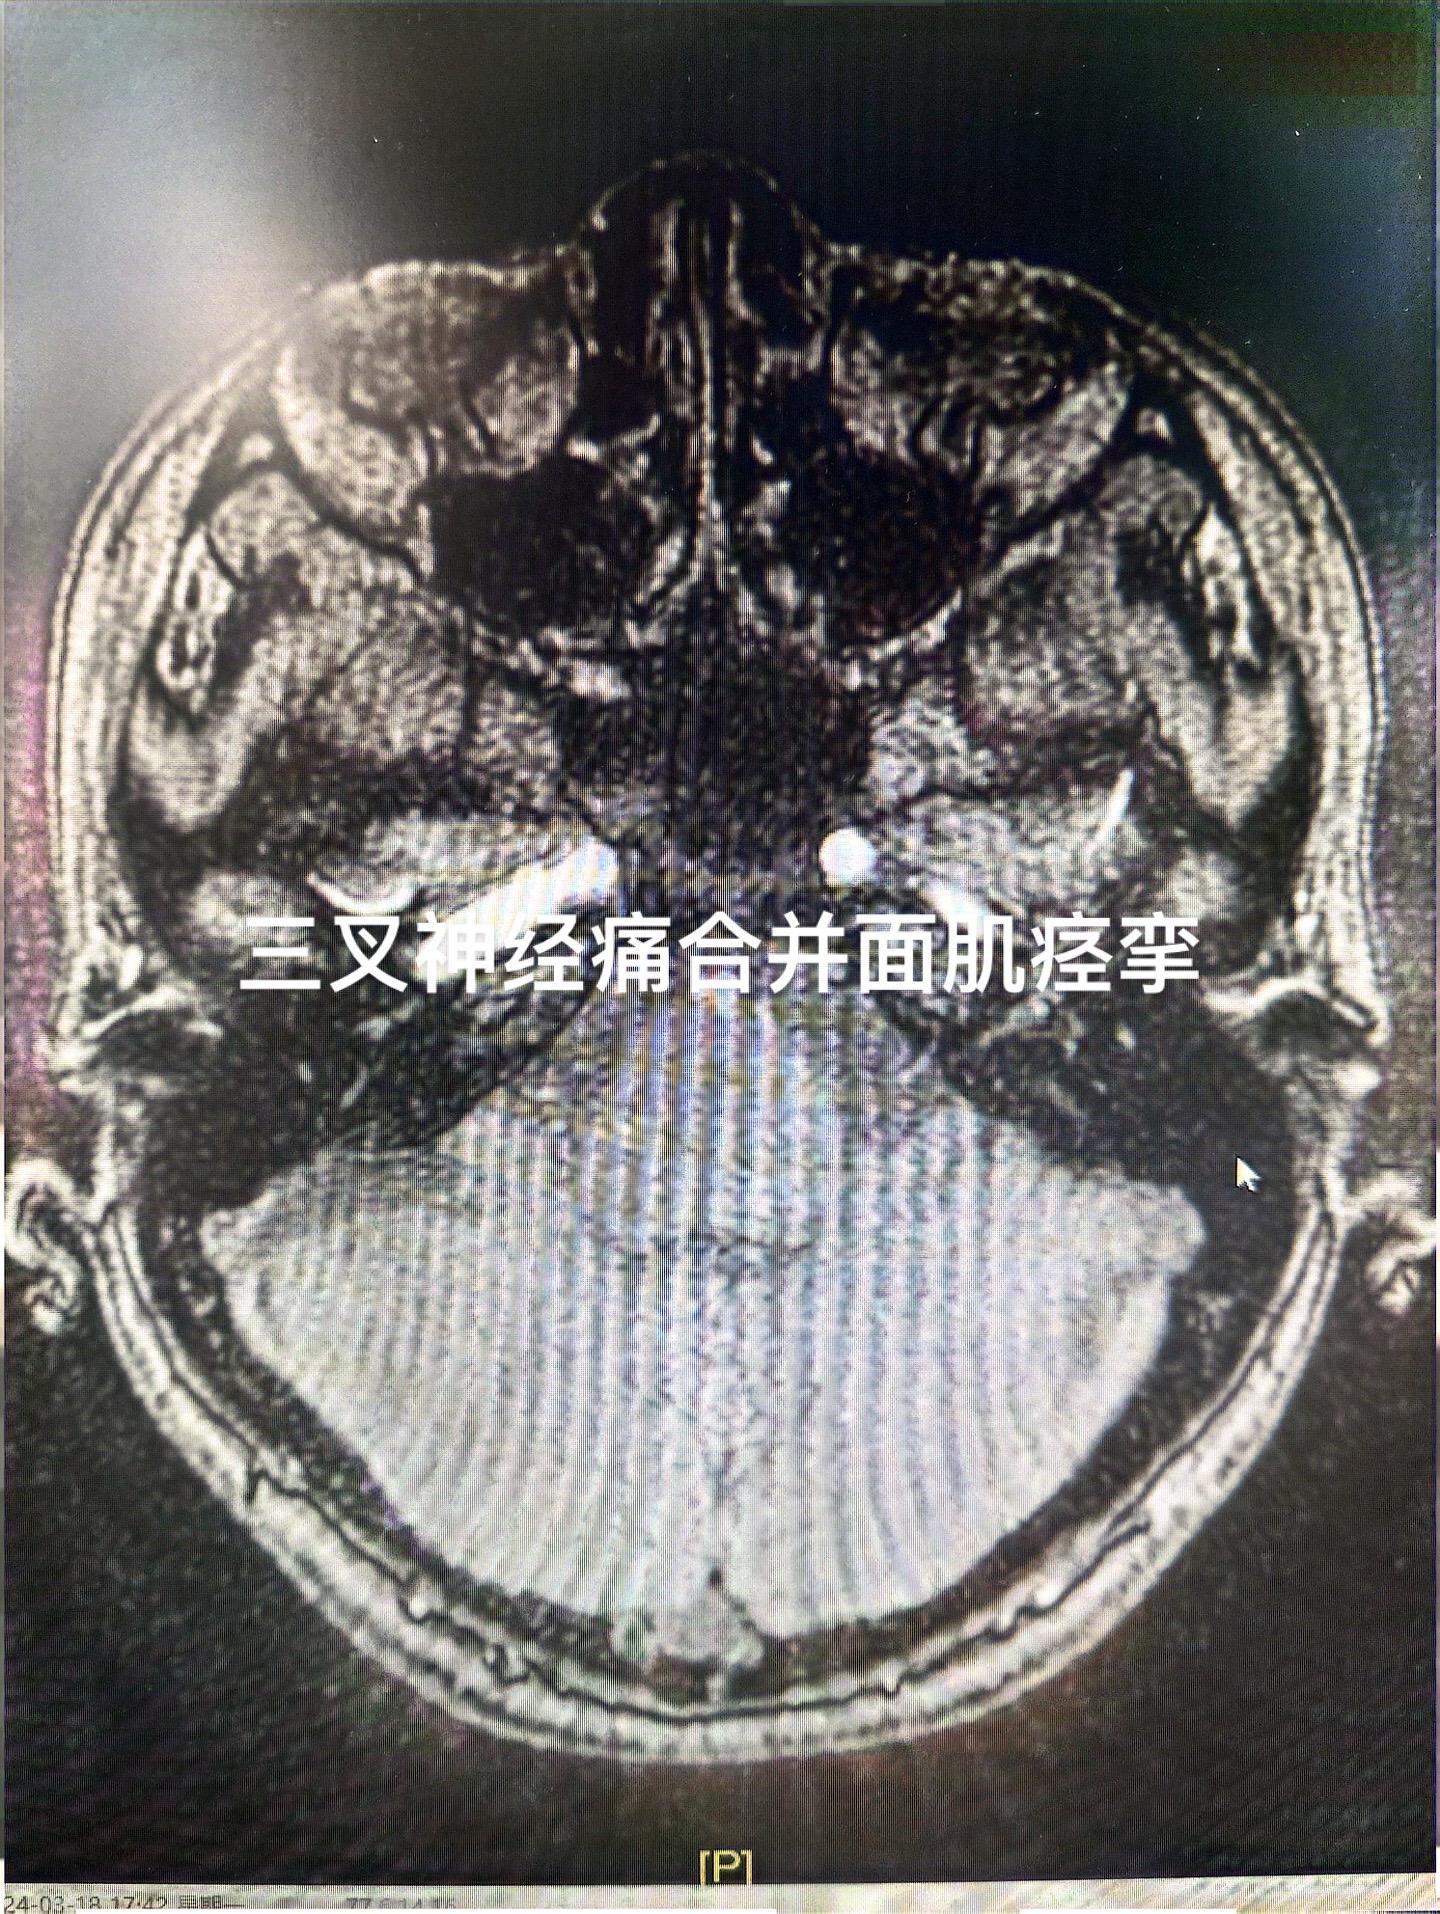

脸疼+脸歪是什么痛苦?本来疼已经很难受,再加上脸歪了简直是“雪上加霜”,一侧三叉神经痛,同时合并面肌痉挛,少见,但是偶尔会碰到,同一侧一个手术切口下一起处理!